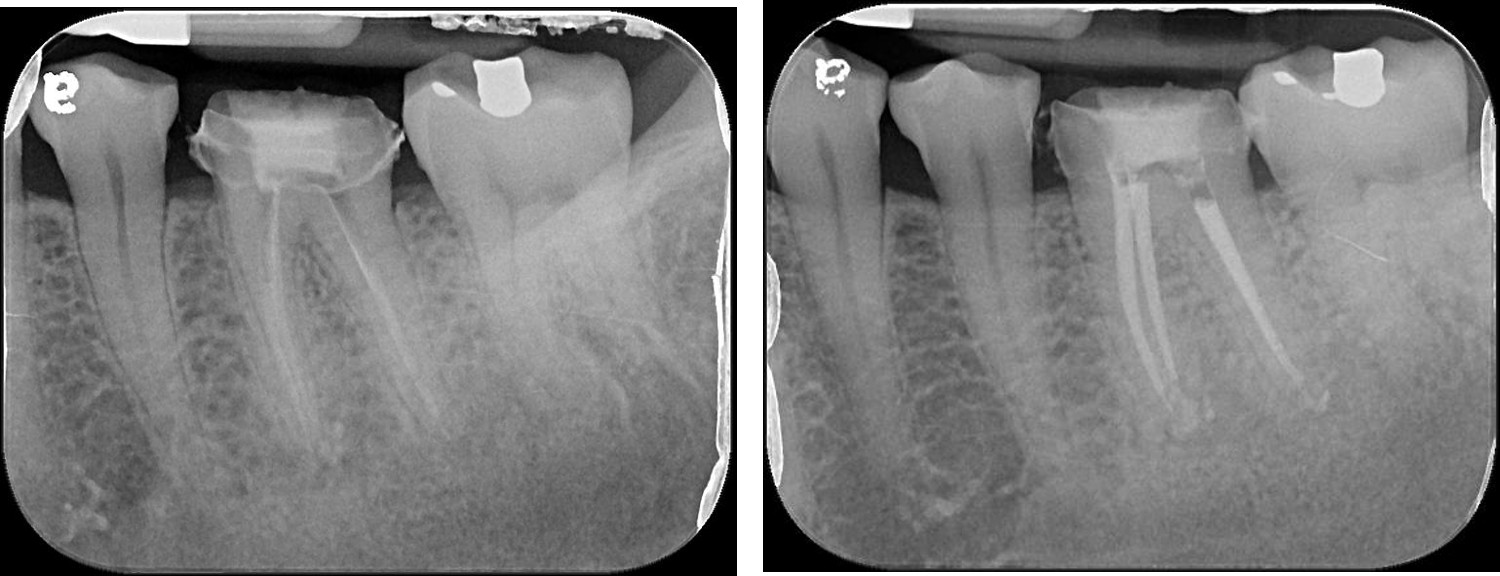

術前、術後比較

顯微鏡輔助根管治療有許多的改變,使得現時的牙髓病治療不但可幫助病患保留更多以前認為無法成功保留的牙齒。